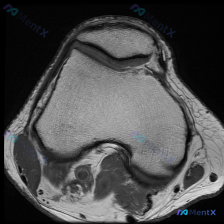

我们先看这张图像本身:

- 扫描层面:膝关节上方,显示髌骨和股骨远端髌股关节面

- 骨质结构:股骨远端股骨滑车沟、双侧股骨髁形态正常,骨皮质光滑,骨髓信号正常,没有局灶异常;髌骨形态完整,轮廓清晰,没有骨质破坏

- 关节软骨:髌股关节软骨信号均匀、厚度轮廓正常,没有看到剥脱、软化或者缺损

- 关节腔与软组织:周围脂肪垫软组织信号正常,关节腔内没有明显异常积液,也没有占位性病变

- 关节对位:髌股关节对位关系良好,没有脱位半脱位

整体读下来,这张图像层面没有看到明确的病理性异常,也没有支持软骨异常的直接影像证据。